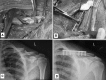

Figures